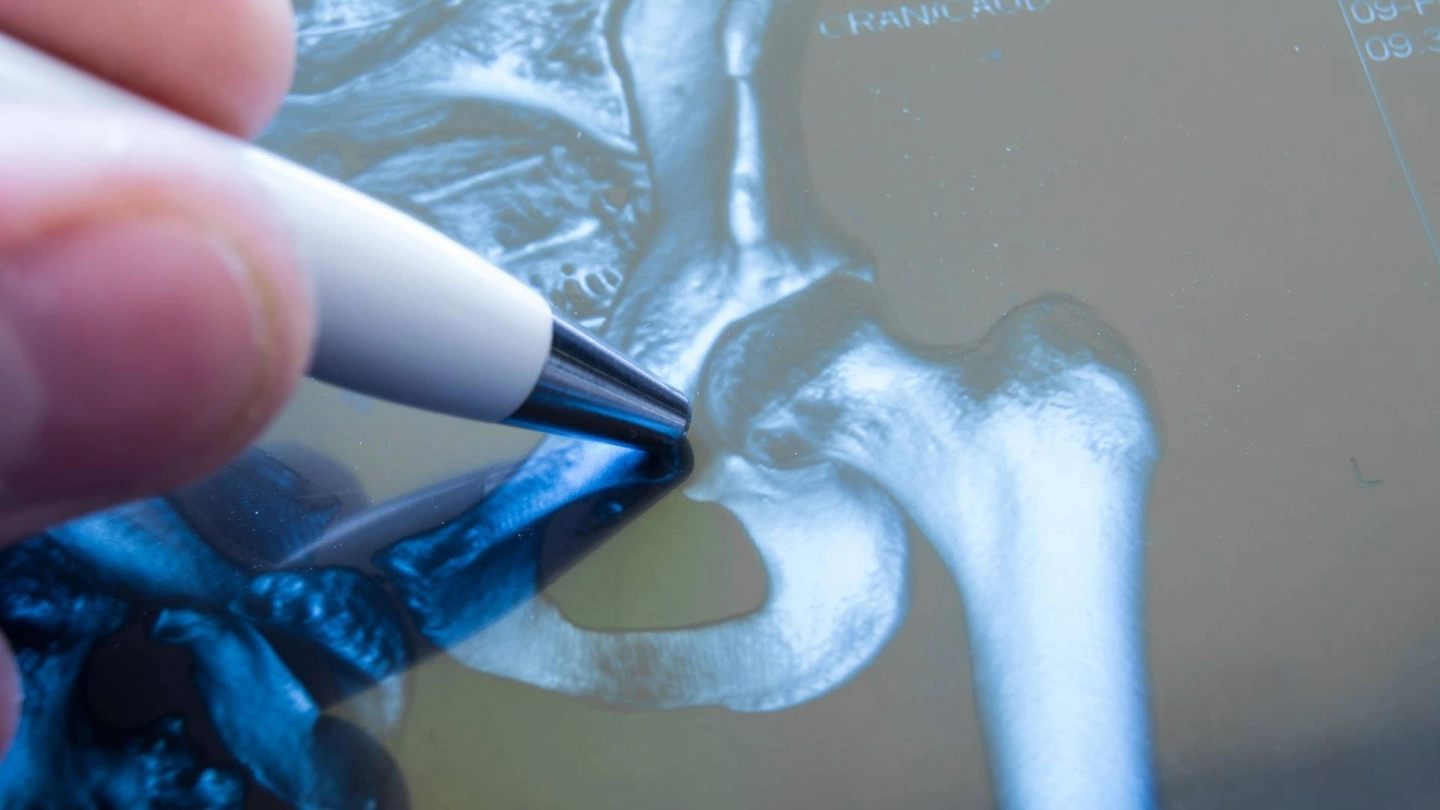

Перелом в области тазобедренного сустава, как правило, можно легко выявить на рентгеновском снимке. Может быть целесообразно сравнить его со снимком здорового тазобедренного сустава.

Только при наличии сомнений применяется компьютерная томография (КТ); в редких случаях также магнитно-резонансная томография (МРТ).

Эти визуализационные методы позволяют определить тип перелома кости. Точная классификация помогает врачам принимать решение о том, какую операцию необходимо провести.